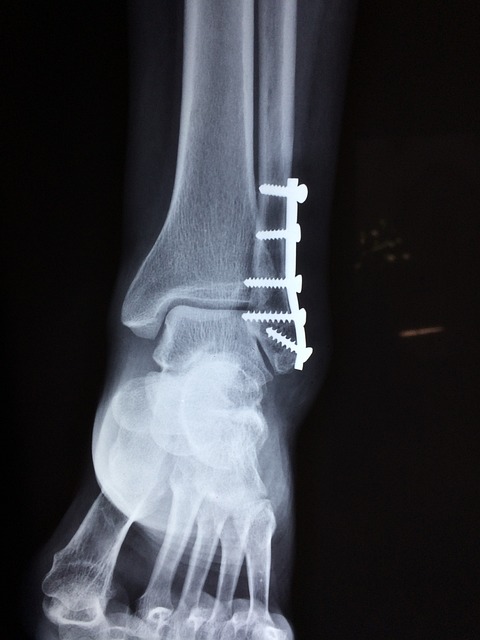

골다공증은 뼈의 밀도가 감소하므로 객관적으로 뼈가 약해지게 됩니다. 이로 인해 일상적인 활동 중에도 간단한 부상이나 낙상에 의해 골절이 발생할 수 있습니다.

갱년기 골다공증으로 인한 후유증 중에서 골절이 발생할 위험성이 높은 부위는 대퇴골(허벅다리 뼈)이나 골반 부위로 여성의 경우, 골다공증으로 뼈의 밀도가 감소하면서 대퇴골이나 골반 부분의 뼈가 쉽게 파괴될 수 있습니다.

특히, 넘어짐이나 낙상과 같은 외부 충격에 노출될 경우 이 부위에서 골절이 발생할 확률이 높아집니다.

갱년기 골다공증이 있는 여성은 골절이 발생했을 때 뼈의 치유가 더 오래 걸릴 수 있습니다. 또한 치유 과정에서 합병증이 발생할 가능성이 높아집니다.

골절로 인한 치유 시간이 길어지면서 통증이 지속될 수 있습니다. 특히, 뼈의 손상이 큰 경우 통증이 심해질 수 있으며 골절 부위의 불편한 움직임을 피하기 위해 주변 근육이 약해지게 됩니다. 이는 움직임의 범위 감소와 관절의 경직을 유발할 수 있습니다.